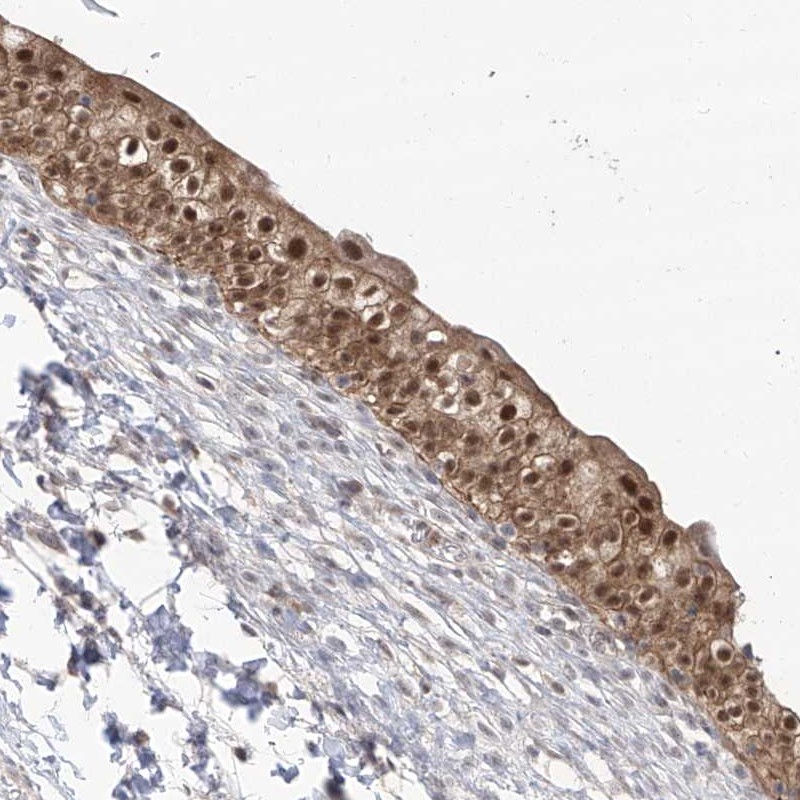

Immunohistochemical staining of human urinary bladder shows distinct nuclear and cytoplasmic positivity in urothelial cells.